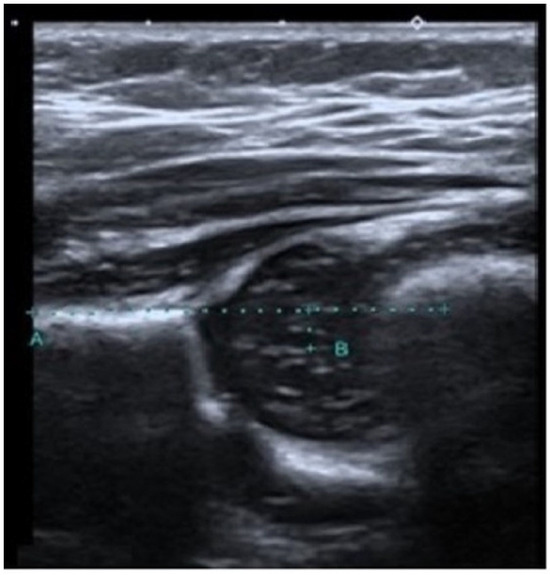

The recently devised technique involved measuring the distance between the central femoral head and a horizontal line that passes through the iliac wing. This measurement is referred to as the FMD value (Figure 1). The determination of the center of the femoral head in hip US pictures was achieved by calculating the average of the longest vertical diameter of the femoral head, as measured in the coronal plane (Figure 2).

Figure 2. The FMD value is measured as 3.3 mm in a 62-day-old type 1 mature hip with an alpha angle of 67 and a beta angle of 53 (FMD refers to the distance that remains between point B and the decussated A line, which is drawn parallel to the femur from the iliac bone. Point B refers to the center of the femoral head).